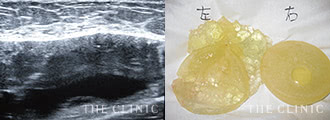

破損し摘出したシリコンバッグ -

破損し摘出したシリコンバッグ

抜去したバッグの報告

術後、実際に取り出した豊胸シリコンバッグの種類や挿入位置についてお伝えします。希望される方には、取り出したバッグを実際にお見せし、トラブルの原因なども詳しくご説明します。

豊胸シリコンバッグ抜去(除去)してみると、挿入時に医師から説明されたというシリコンバッグの種類やサイズと違っているケースも珍しくありません。